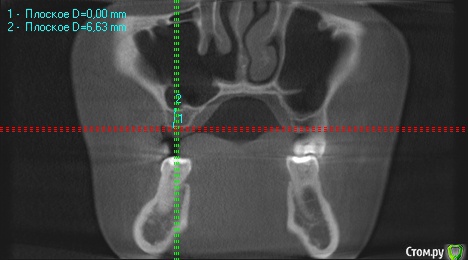

wladdX Опубликовано 27 февраля, 2019 Поделиться Опубликовано 27 февраля, 2019 (изменено) Скриншоты Сколько успел Изменено 27 февраля, 2019 пользователем wladdX Ссылка на комментарий

red_butler Опубликовано 27 февраля, 2019 Поделиться Опубликовано 27 февраля, 2019 соустье нужно посмотреть, но предварительно - не вижу препятствий для проведения открытого синуслифта Ссылка на комментарий

kramer Опубликовано 27 февраля, 2019 Поделиться Опубликовано 27 февраля, 2019 Закрытый синус-лифт + 10 мм имплантат Ссылка на комментарий

red_butler Опубликовано 27 февраля, 2019 Поделиться Опубликовано 27 февраля, 2019 8 мм имплант и закрытый синус без графта Ссылка на комментарий

колесников Опубликовано 3 марта, 2019 Поделиться Опубликовано 3 марта, 2019 У вас речь идёт об одном импланты в области 16. Одиночный короткий Имплант не рекомендуется ни одним из производителей имплантов. Открытый синуслифтинг не показан из за особенностей строения пазухи в этой области,показан закрытый. Так же рекомендовал бы Астра тек,4.5х9. А также:дистализация 17го и имплантация в области 47.. либо удаление 17го,имплантация 17,16,47 Ссылка на комментарий